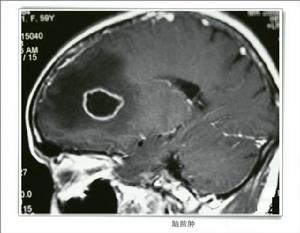

2.顱腦CT掃描 腦膿腫的CT表現依膿腫發展階段而異。急性化膿性腦炎階段 病灶表現為邊界模糊的低密度區 不強化。化膿與膿腫壁形成期,在低密度區周圍可顯示等密度膿腫壁 膿腫壁可輕度強化,強化厚度多不均勻,膿腫較小時,可呈結節狀強化,強化厚度多不均勻,膿腫較小可呈結節狀強化 膿腫周圍有不規則腦水腫帶,多較顯著 CT不僅可以確定膿腫的存在、位置、大小、數目、形狀及其周圍腦組織水腫情況 而且可幫助選擇治療方法和確定手術時機。

3.MRI檢查 MRI檢查有其獨到的優點 不僅在膿腫形成期,於T2加權圖像上能顯示壞死區周圍的屬特徵性的低信號帶,而且在腦炎期也能根據T1和T2弛豫時間的變化,做出早期診斷。即在T1加權圖像上可見白質內不規則的略低信號區 在T2加權圖像上呈明顯的高信號,腦炎中心區為稍低信號,並有占位效應。若採用Gd-DTPA增強,則在T2加權圖像上可以看到不規則的瀰漫性強化,並有助於臨床治療上的參考。